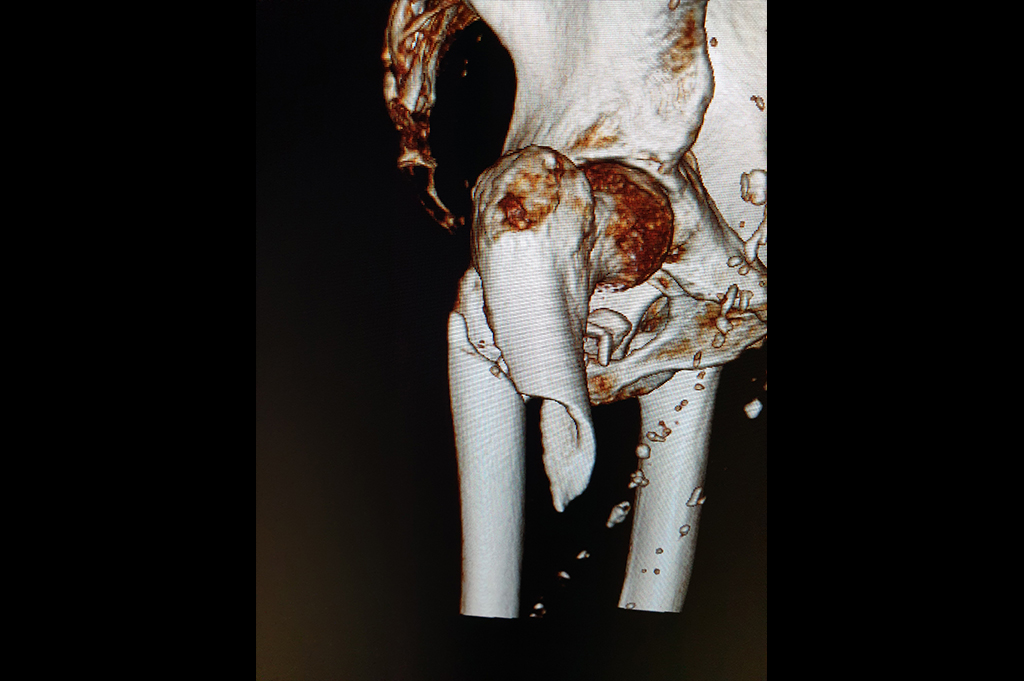

Periprosthetic Fracture THR